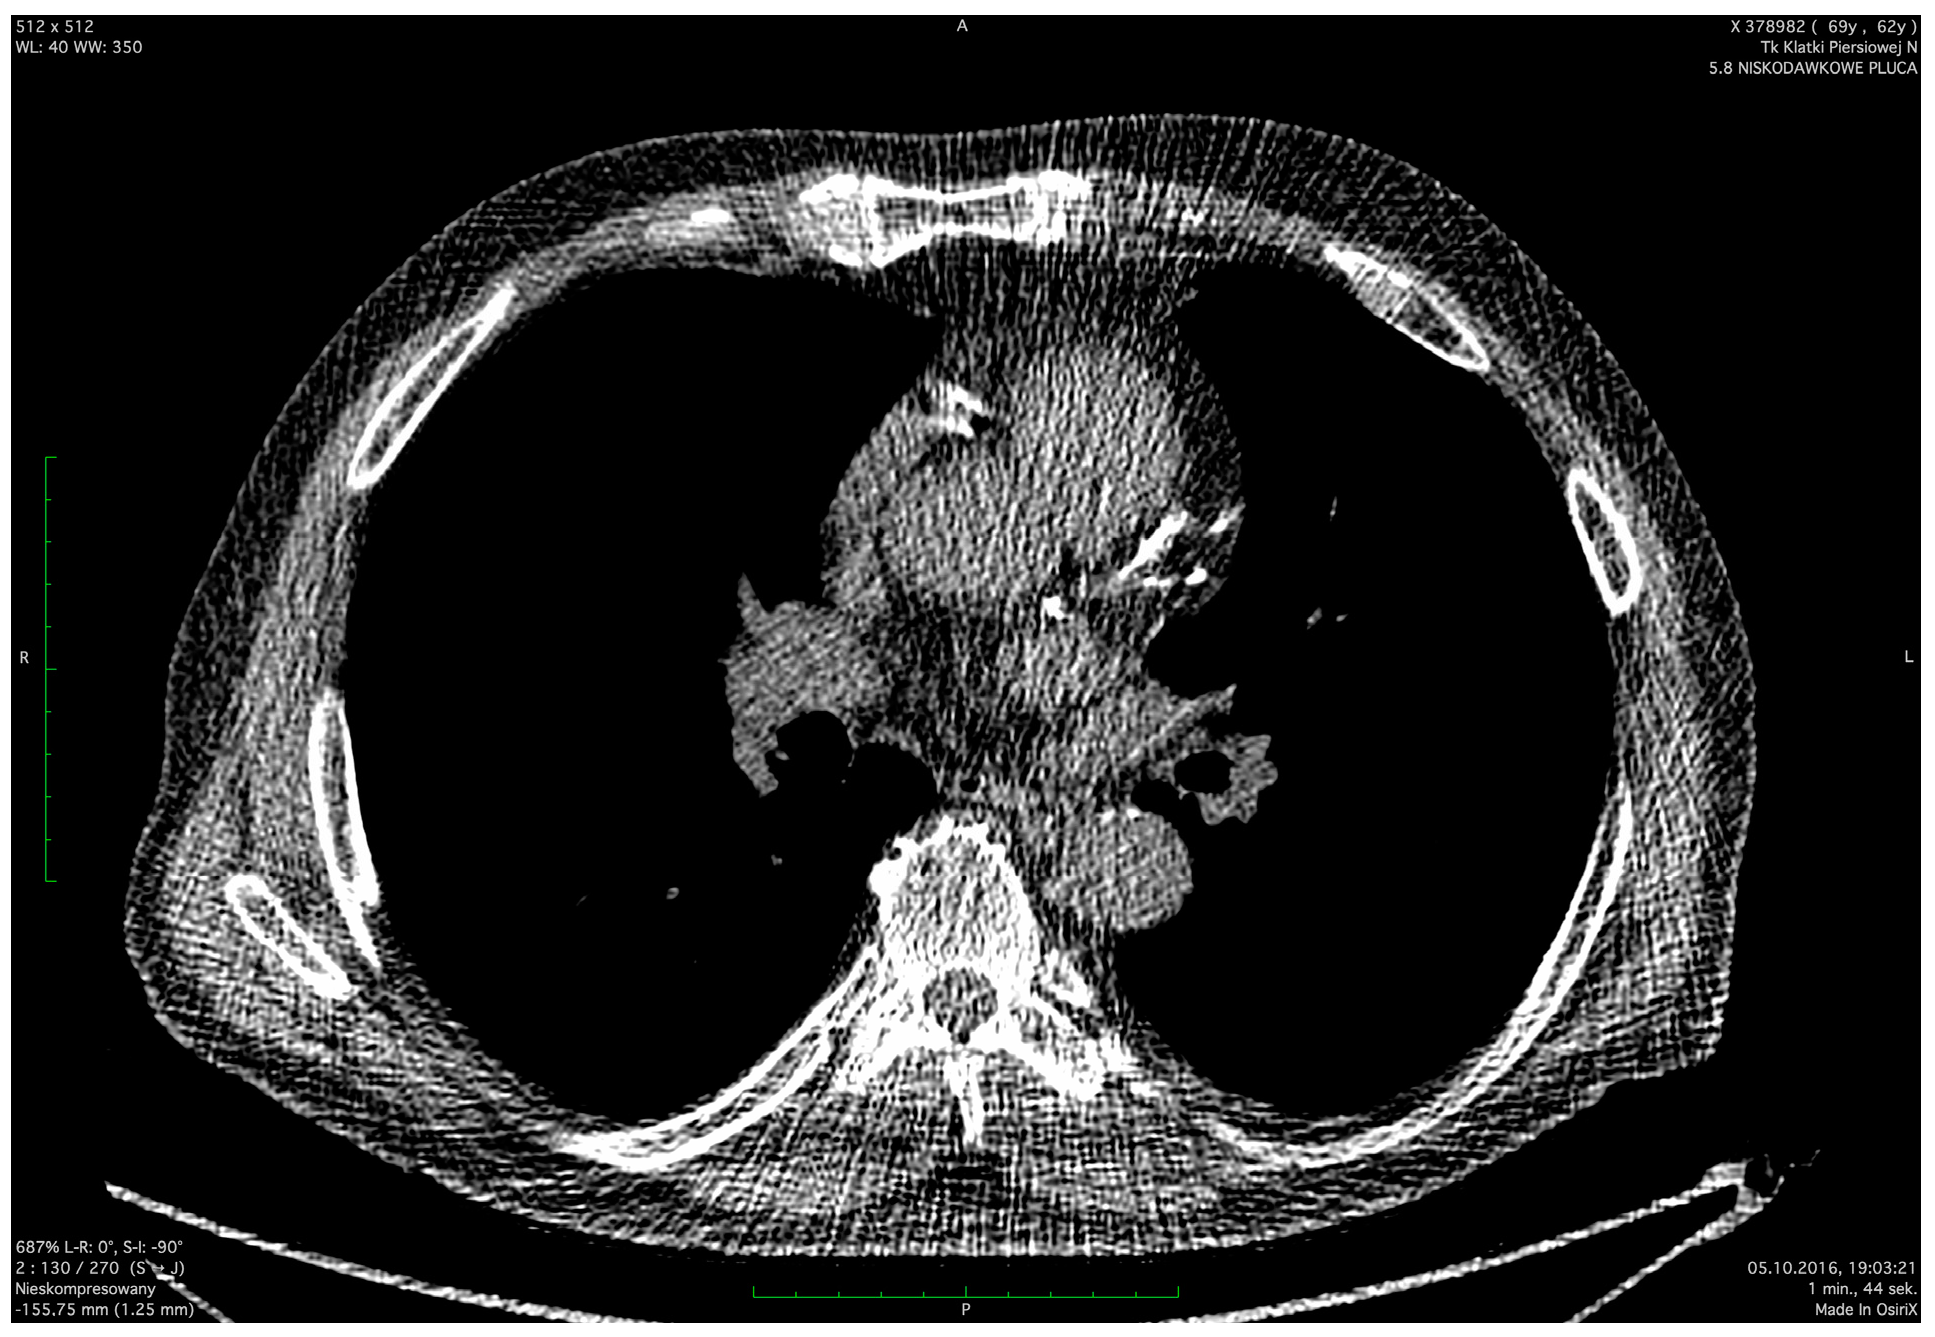

| CAC | ||||

|---|---|---|---|---|

| 0 | 1–3 | 4–6 | 7–12 | |

| Number of observations (n) | 214 (53%) | 106 (26%) | 48 (12%) | 36 (9%) |